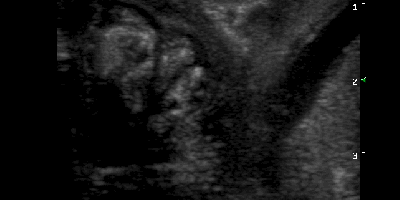

Κατηγορία: Abdominal Ultrasound